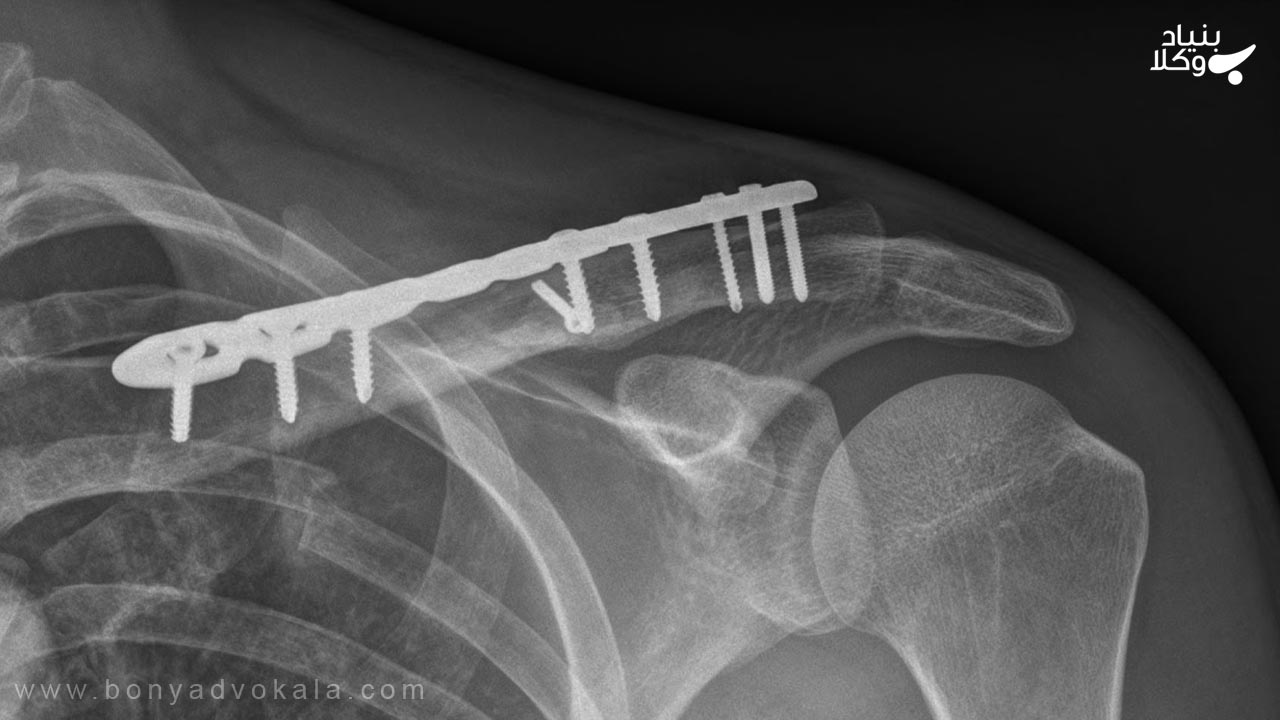

در صورتی که هر یک از استخوانهای ترقوه بشکند و با کار گذاشتن پلاتین درمان شود و درمانش بدون هیچ عیبی باشد در این صورت دیه آن چهار درصد دیه کامل است اما اگر شکستگی استخوان ترقوه طوری باشد که حتی بعد از کار گذاشتن پلاتین هم درمان نشود و یا با عیب درمان شود در این حالت دیه آن نصف دیه کامل انسان خواهد بود.

دیه شکستگی استخوان ترقوه با پلاتین

با توجه به توضیحات قسمت قبل، اگر آسیب وارد شده باعث شود که استخوان ترقوه بشکند و برای درمان آن از پلاتین استفاده کنند، در صورتی که بعد از کار گذاشتن پلاتین بدون هیچ عیبی درمان شود، در این شرایط دیه شکستن استخوان ترقوه با پلاتین چهار درصد دیه کامل انسان خواهد بود اما اگر حتی با کار گذاشتن پلاتین استخوان ترقوه درمان نشود و یا با عیب درمان شود در این صورت دیه آن نصف دیه کامل انسان است.